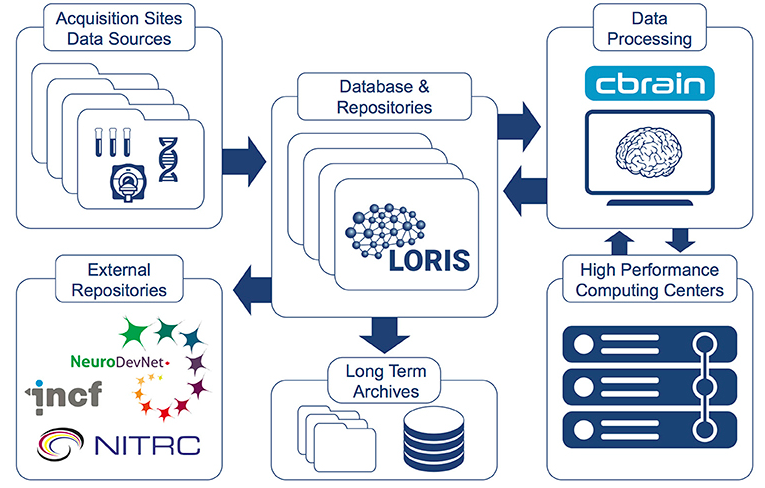

LORIS-CBRAIN INTEGRATION

What can LORIS do (pointform)

- Long Term Storage - Large datasets are valuable assets (e.g. ADNI)

- Data Sharing - Cross project collaborations

- Heterogeneous Data Management - Single platform for MRI, PET, Clinical & Genetics data

- Processing Platform - Seamless serving of data to processing environments

Data Sharing Initiatives

Public Data Repositories

Collaborative Data releases

CBRAIN hooks